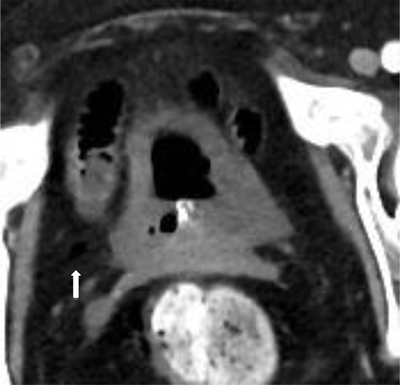

Figure 3

One-week later follow-up CT was performed, this showed a spontaneous healing of the bladder wall with only a small residual focus of free air in the Retzius space on the right (white arrow).